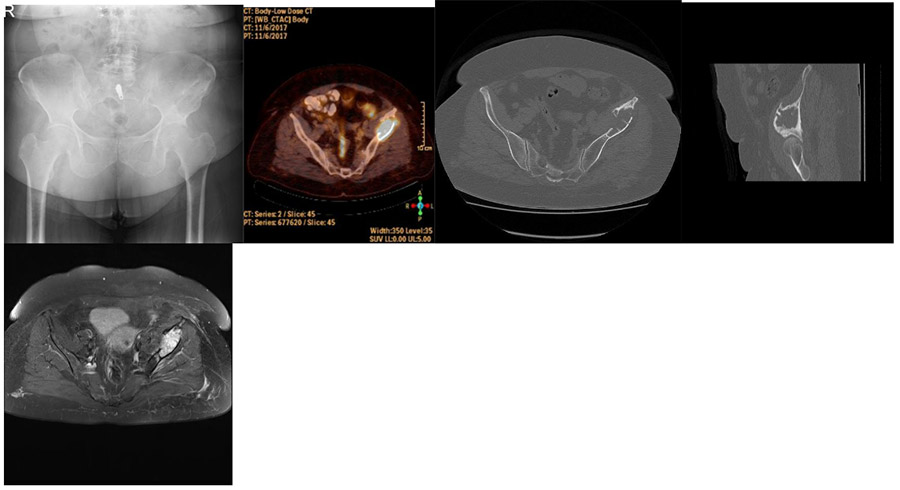

CASE 15: Fracture development due to left pelvic bone (pelvis) metastasis of breast cancer.

Before the surgery: X-ray shows damage to the left pelvic bone, PET-CT shows significantly increased activity in the same area, CT scan shows degeneration and fracture in the upper region of the left hip joint, and MRI shows tumor tissue in the same area.